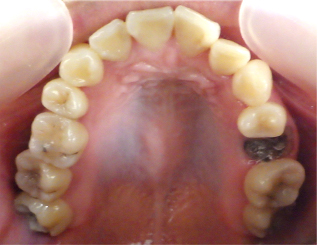

- ブリッジ 症例写真 B-0111フルジルコニア7本 女性モニターの方です。

この方は奥歯に虫歯と歯の欠損がありました。 上下ともブリッジで治療しました。 当院では上下のブリッジ治療を同時進行で行いますので、通院回数が少なく済みます。 また、1回目の治療時に仮歯を入れますので、すぐに見た目が気にならなくなります。 治療回数は5回でした。